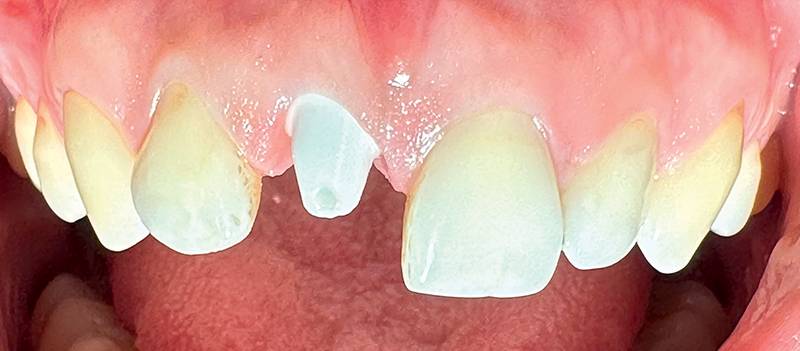

Caso 2: Una paziente di 33 anni si presentava con corona clinica del dente 11 scolorita, associata ad una linea del sorriso alta, che rappresentava una sfida per il risultato estetico. Il dente era associato a riassorbimento apicale, cisti e sintomi dolorosi. Veniva estratto e la paziente riceveva un impianto SDS. L'intervento seguiva scrupolosamente il protocollo di perforazione ossea suggerito dal produttore, e l'intervento mini-invasivo manteneva intatte la parete buccale dell'alveolo dentale. La competenza del chirurgo si rivelava fondamentale per ottenere un risultato estetico favorevole, fin dai primi passi. Lo spazio tra l'impianto e la parete vestibolare (circa 0,5-1 mm) veniva riempito con matrici PRF, per stimolare la formazione di nuovo osso. In questo caso non era necessaria la sutura. Dopo 3 mesi l’impianto era preparato e la paziente riceveva la corona definitiva. La paziente era soddisfatta del trattamento (Fig. 3-10).

Fig. 3 (caso 2) - Procedura mini-invasiva con conservazione della teca ossea vestibolare

Fig. 4 (caso 2) - Osteotomia secondo protocollo SDS

Fig. 5 (caso 2) - Impianto SDS

Fig. 6 (caso 2) - Situazione immediatamente dopo il posizionamento dell'impianto e l'inserimento di matrici PRF